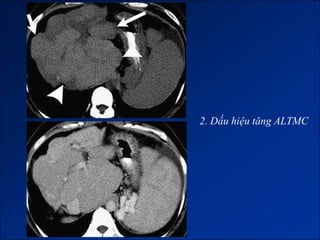

Hình ảnh trên CLVT

- Giai đoạn sớm:

+ Gan to.

+ Tăng tỷ trọng do xơ hóa.

- Giai đoạn muộn:

+ Gan biến đổi hình thái và đường bờ.

+ Dấu hiệu tăng ALTMC.

+ Dấu hiệu khác:

Dịch ascite – Lách to – Dày thành TM.

Nốt tân tạo.

Biến chứng (HCC).

2. Dấu hiệu tăng ALTMC